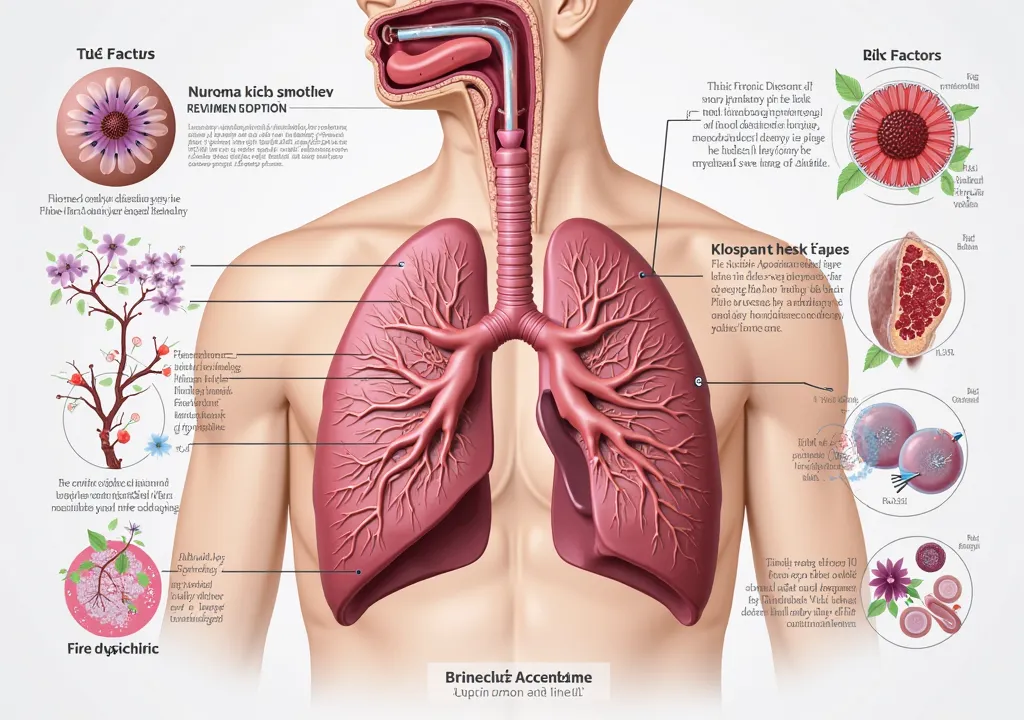

Make a folder about bacterial pneumonia

Make a folder about bacterial pneumonia